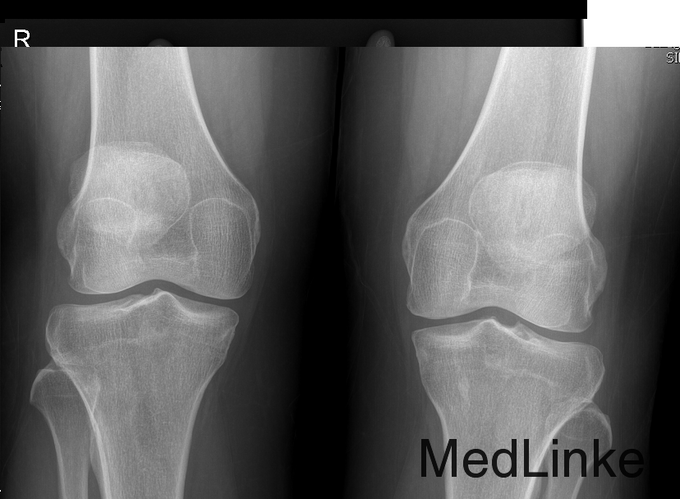

心肺腹查体未见明显异常。双肩关节无压痛,双肘关节压痛+,肿胀+,双腕关节压痛++,肿胀++;关节活动受限,双腕关节及双侧第4、5掌指关节、指间关节畸形,双侧掌指关无压痛,无肿胀;关节活动尚可,双膝关节无肿胀、压痛,皮温无升高,浮膑征-,双踝关节肿胀++,压痛++。 查全血常规正常; 电解质、肾功能正常。 乙肝两对半提示为小三阳,HBV-DNA阴性, 肝功能ALT 67 U/L; 炎症指标:C反应蛋白测定 12.6mg/L ↑; 类风湿因子测定 64.4IU/mL ↑; 红细胞沉降率 20mm/h ; 抗核抗体定性阴性-;抗ds-DNA定量 15.4IU/ml ;ENA抗体阴性-; 补体C3含量测定 695mg/L ↓;补体C4含量测定 178mg/L; 直接抗人球蛋白试验阳性+;间接抗人球蛋白试验阴性; 免疫球蛋白IgA、IgM、IgG均正常; 双足部、双膝关节、手正位放射常规照片:双手、双腕及双足跖趾关节改变,符合类风湿关节炎。